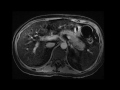

Autoimmune pancreatitis

Patient with chronic abdominal pain. MR images demonstrate diffuse enlargement of the pancreas with a subtle low signal rim surrounding its margin. This surrounding rim demonstrates increasing enhancement on the delayed post-gadolinium images. This constellation of findings is highly suggestive of autoimmune pancreatitis.